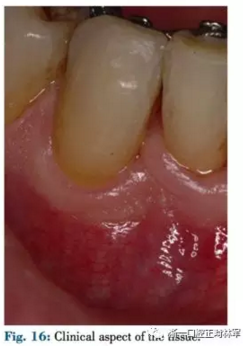

患者42-43區(qū)有復發(fā)性膿腫,42為兩壁骨袋,遠中牙周探診9mm(圖12),43探診提示有附著喪失但較穩(wěn)定。患者要求治療膿腫并排齊下頜牙列,因此決定通過拔除42解決擁擠。方案不采用GTR保留牙齒,通過正畸拔除42改造骨缺損形態(tài),獲得軟硬組織,避免拔牙區(qū)由于組織的萎縮出現(xiàn)不美觀的裂口。通過鄰牙的擠壓重建生理性鄰間解剖結構?;颊呤褂蒙鄠日辰?,初期通過牽引42,43以排齊并修復43近中骨缺損。隨后緩慢牽引42,42處加轉矩扭轉牙以增加頰側骨量并減少軟組織塌陷,避免后期拔牙由于骨皮質薄導致的裂縫,先用0.016TMA后用0.017×0.017帶鉤TMA完成(圖13-16)。